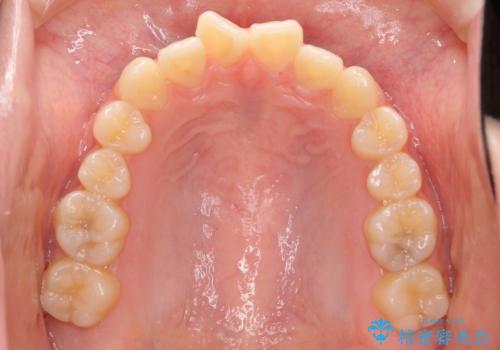

話しにくいオープンバイト ワイヤー装置による抜歯矯正治療

- 前歯のオープンバイトを気にして来院された患者様です。

上下前歯の前後位置が大きくずれていたため、上顎左右第一小臼歯2本を抜歯してワイヤー装置による矯正治療を行うこととしました。

オープンバイトの原因は舌の突出癖であり、癖が改善されないと治療経過に影響を及ぼすため、舌のトレーニングを指示しました。

なかなか癖が改善されず、トレーニングも断続的に行ったため、治療期間は長期化しました。